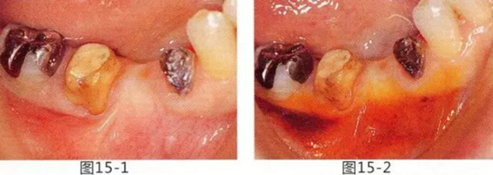

頰系帶附著于高位,其周圍附著齦缺失的病例

頰系帶延伸至游離齦,附著齦缺失的病例中,為了完成之后修復體能夠保持長期清潔,將系帶切除,并通過FGG(游離齦移植)增加附著齦。

圖15-1,2 右下6近中部的頰系帶延伸到游離齦,附著齦也處于缺失狀態(tài)。如果在這個狀態(tài)下進行修復,會使清潔變得困難,容易引發(fā)牙齦萎縮。

圖15-3 切除系帶。為了獲得附著齦,進行游離齦移植。

圖15-4 手術完成6個月后,佩戴修復體時的狀態(tài)。